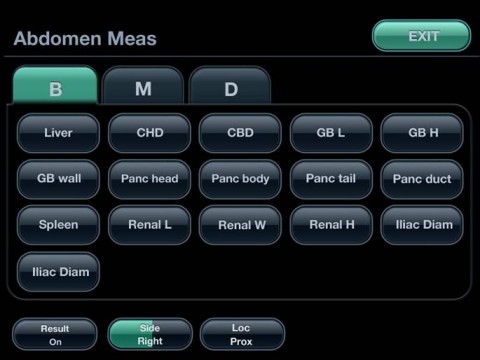

ПАКЕТ ПРОГРАММ ОБЩИХ ИЗМЕРЕНИЙ У АППАРАТА DC7 Миндрай

• Общее измерение для B-режима

• Общее измерение для M-режима

• Общее измерение для цветного доплера

• Общее измерение для спектрального доплера

ПАКЕТ ПРОГРАММ КЛИНИЧЕСКИХ ИЗМЕРЕНИЙ:

• Акушерских исследований

• Кардиологических исследований

• Гинекологических исследований

• Исследований периферических сосудов

• Исследований малых органов

• Урологических исследований

• Ортопедических исследований